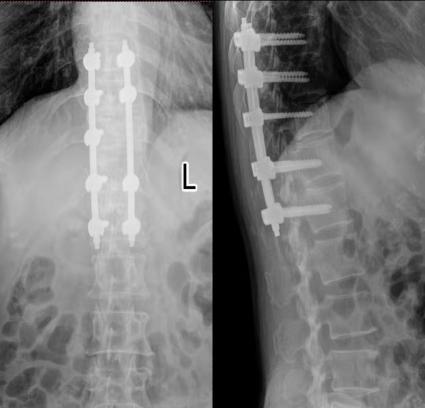

谭磊副院长为患者家属详细分析了病情,考虑到椎体侵袭性血管瘤出血量大及患者的家庭经济情况,并制定了“胸椎后路椎体内肿物切除、植骨融合内固定术+右侧髂骨取骨术”的手术治疗方案。

在麻醉科、重症医学、心内科、输血科的支持下,手术在2019年10月30日8时进行。 术中,谭磊副院长带领团队与麻醉医师、输血科、手术护理团队默契配合,历时三小时,高效、快速的完成了手术。

术后患者背部疼痛消失,双侧足底麻木感逐渐缓解,没有出现任何并发症,术后第二天拔除引流管,在支具保护下行走,术后第七天出院。

术后复查x线、CT